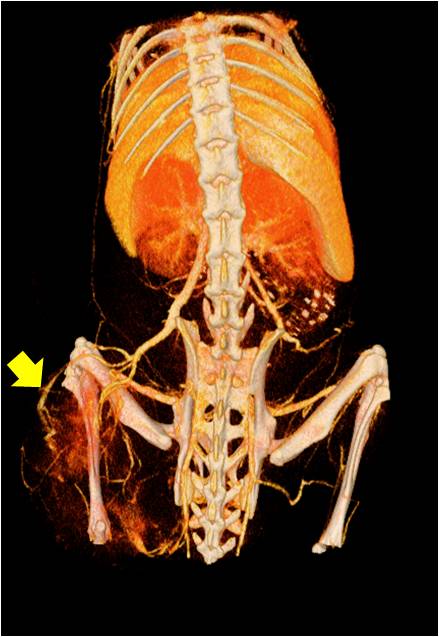

腫瘤血管生成

肺轉(zhuǎn)移

小鼠模式,22.5μm像素

正常

8天 14天

無(wú)造影劑注入 造影劑注入